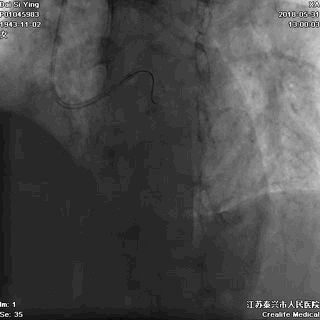

广东佛山有位姓谭的男子,年仅45岁,只身一人出差来江苏泰兴,突发胸痛,9小时后就诊于江苏省泰兴市人民医院,心电图诊断为“急性心肌梗死”。

他在这里举目无亲,该怎么办?

听了医生的建议后,他当机立断,自己签字接受急诊手术。这是一个大胆而又明智的决定!医生立即为谭某进行了介入手术,打开了闭塞的血管,恢复了心肌的血液供应。

闭塞的前降支血管开通了,心肌的血供恢复了

记住:出门在外发生“急性心梗”,如果身边没有亲人,能够救你一命的只有医生!请相信他,果断签字手术。不要等待配偶,不要等孩子,更不要犯傻地要求回当地手术。命运此刻就掌握在你自己手中。